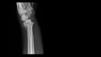

F4

Fig. 4.:

Radiographs of injury and after 6 months.